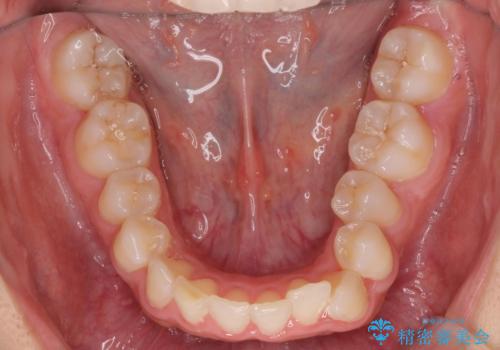

- 前歯のがたつきと突出を主訴に来院。

歯を抜かずに非抜歯で治療しました。